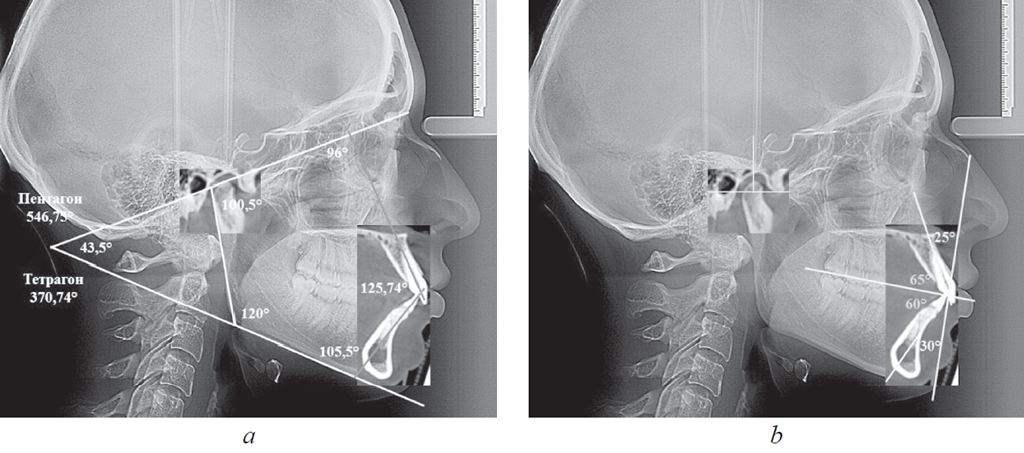

В вертикальном направлении соединяли точки N и Pg, полученную линию обозначали как «вертикальную линию лица». Касательная линия к ветви нижней челюсти (Ar – T1) с мандибулярной плоскостью образовывала угол нижней челюсти (рис. 1).

Рис. 1. Основные точки (a); линии используемые в качестве основных ориентиров для сопоставления рентгенограмм (b)

Fig. 1. Main points (a); lines used as the main reference points for the comparison of radiographs (b)

Рис. 3. Измерение гнатических углов (а); оценка положения сустава и резцов на совмещенных рентгенограммах (b)

Fig. 3. Measurement of gnatic angles (a); assessment of the position of the joint and incisors on combined radiographs (b)

Полученные снимки позволяли проводить линейные и угловые измерения, а также переносить данные томограмм на телерентгенограммы. Как отмечено выше, рекомендуем измерять угол между линиями МL и KFL, а также углы, образованные линиями резцов с указанными линиями (верхнерезцовый и нижнерезцовый). В совокупности с межрезцовым углом нами предложено оценивать сумму указанных четырех углов (тетрагональный показатель), их величины могут быть использованы для определения типа роста лицевого отдела головы. К такому же показателю можно отнести сумму пяти углов: верхнерезцового, межрезцового, нижнерезцового, нижнечелюстного и суставного (пентагональный показатель).